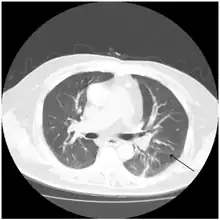

Chest CT three months after admission with resolved ground glass infiltrates revealing the initial atelectasis of the left lower lobe present two months prior to admission (arrow).